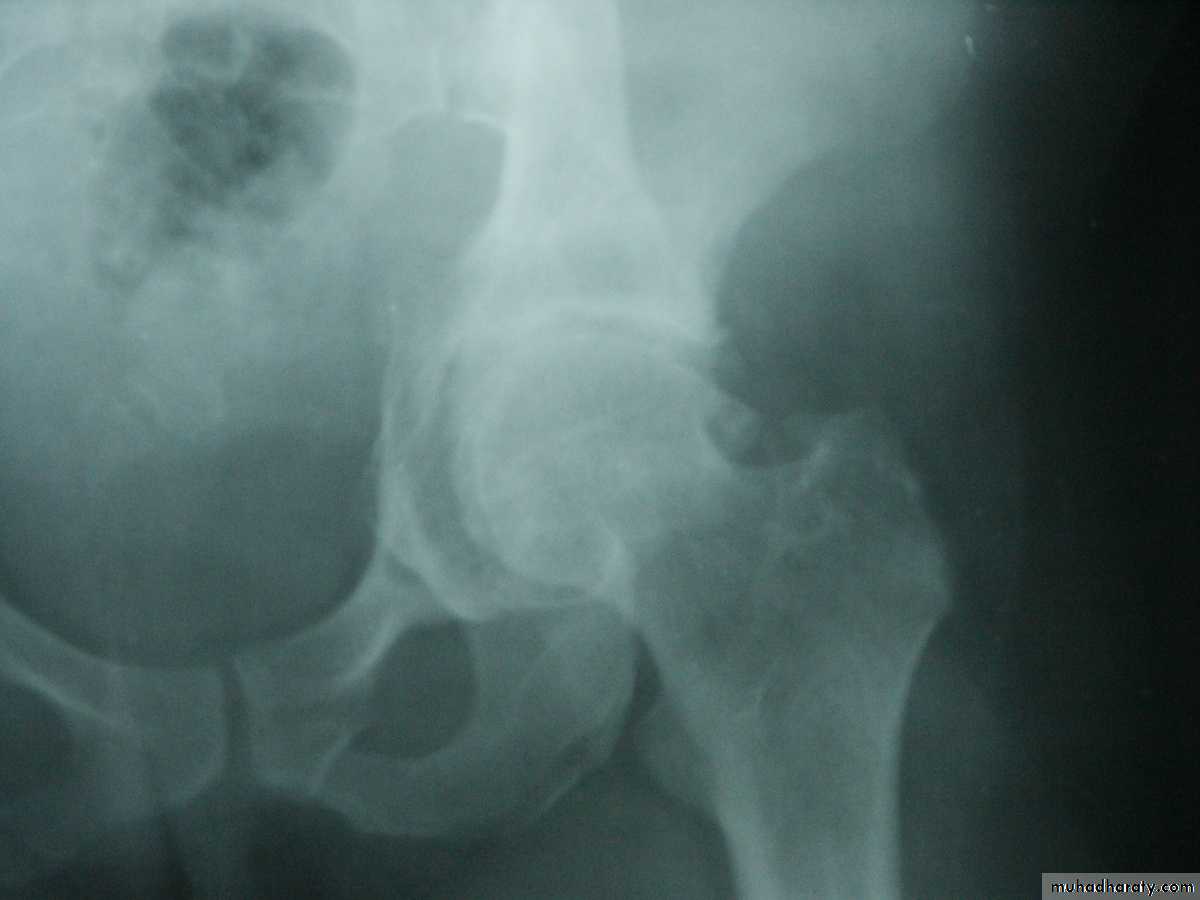

HIP DISLOCATION

Traumatic Dislocations of the hip.

Posterior.

Anterior.

Central.

Posterior dislocation:

Mechanism of injure:

4 out of 5 traumatic hip dislocations are posterior.

Usually occur in road traffic accident when the knee striking the dashboard

the femoral head is forced out of its socket sometimes associated with fracture.

Clinically:

O\E

Leg is short, internally rotated, adducted ,

and slightly flexed hip.

Radiological examinations

X-R AP view we can see the dislocation with or without associated fracture posterior wall of the acetabulum,

or fracture head of the femur,

And neck of femur.